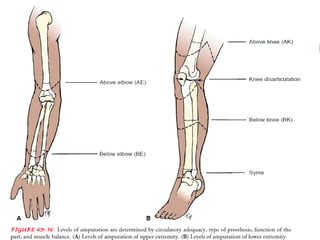

– X-ray of affected joints: osteophyte formation, joint

space narrowing, subchondral sclerosis and cysts

X ray finding

52

X ray finding of OA….

53

54